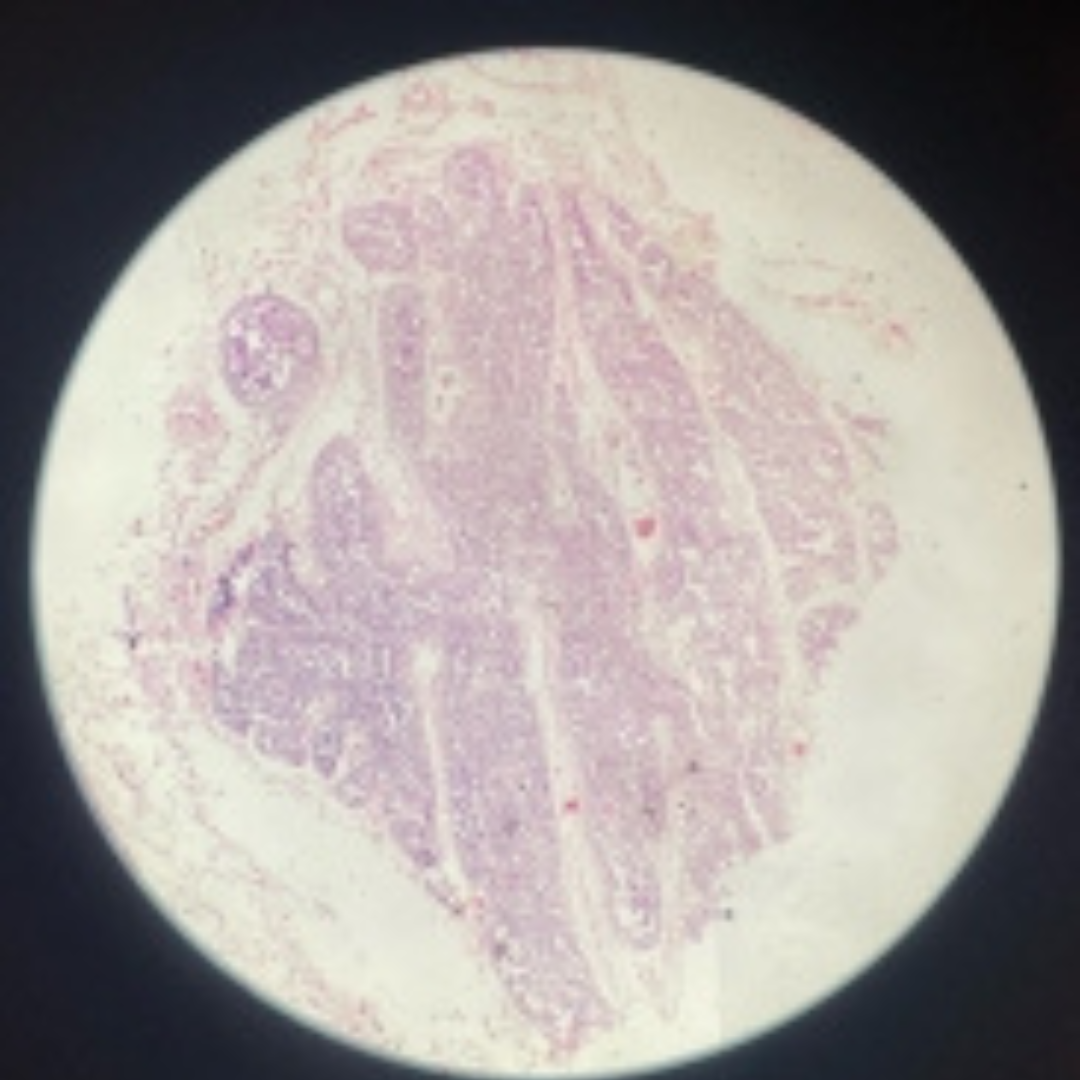

Lymph Node

11

New cards

Lymph Node

12

New cards

Lymph Node

13

New cards

Lymph Node

14

New cards

Lymph Node

15

New cards

Lymph Node